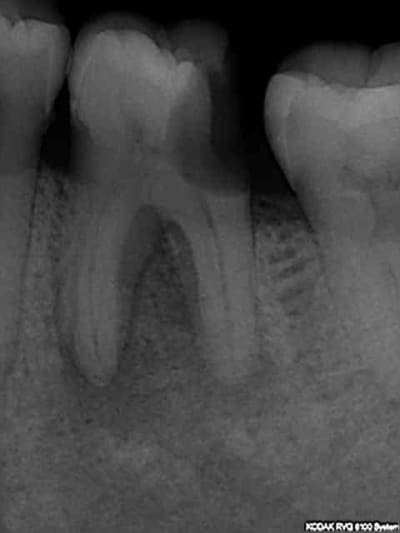

Sur la 26 ce qu'il faut faire, sur la 27 ce qu'il ne faut pas faire. Ca va rentrer oui ou non ?-))

Je suis paumé là. Signes d'appel sur 24 (abcès en vesti), 45 (mobilité), 44 pulpite + antécédents de soins intensifs. Je cote quoi là ? (pour une fois toutes les endos ne sont pas pourries).-))